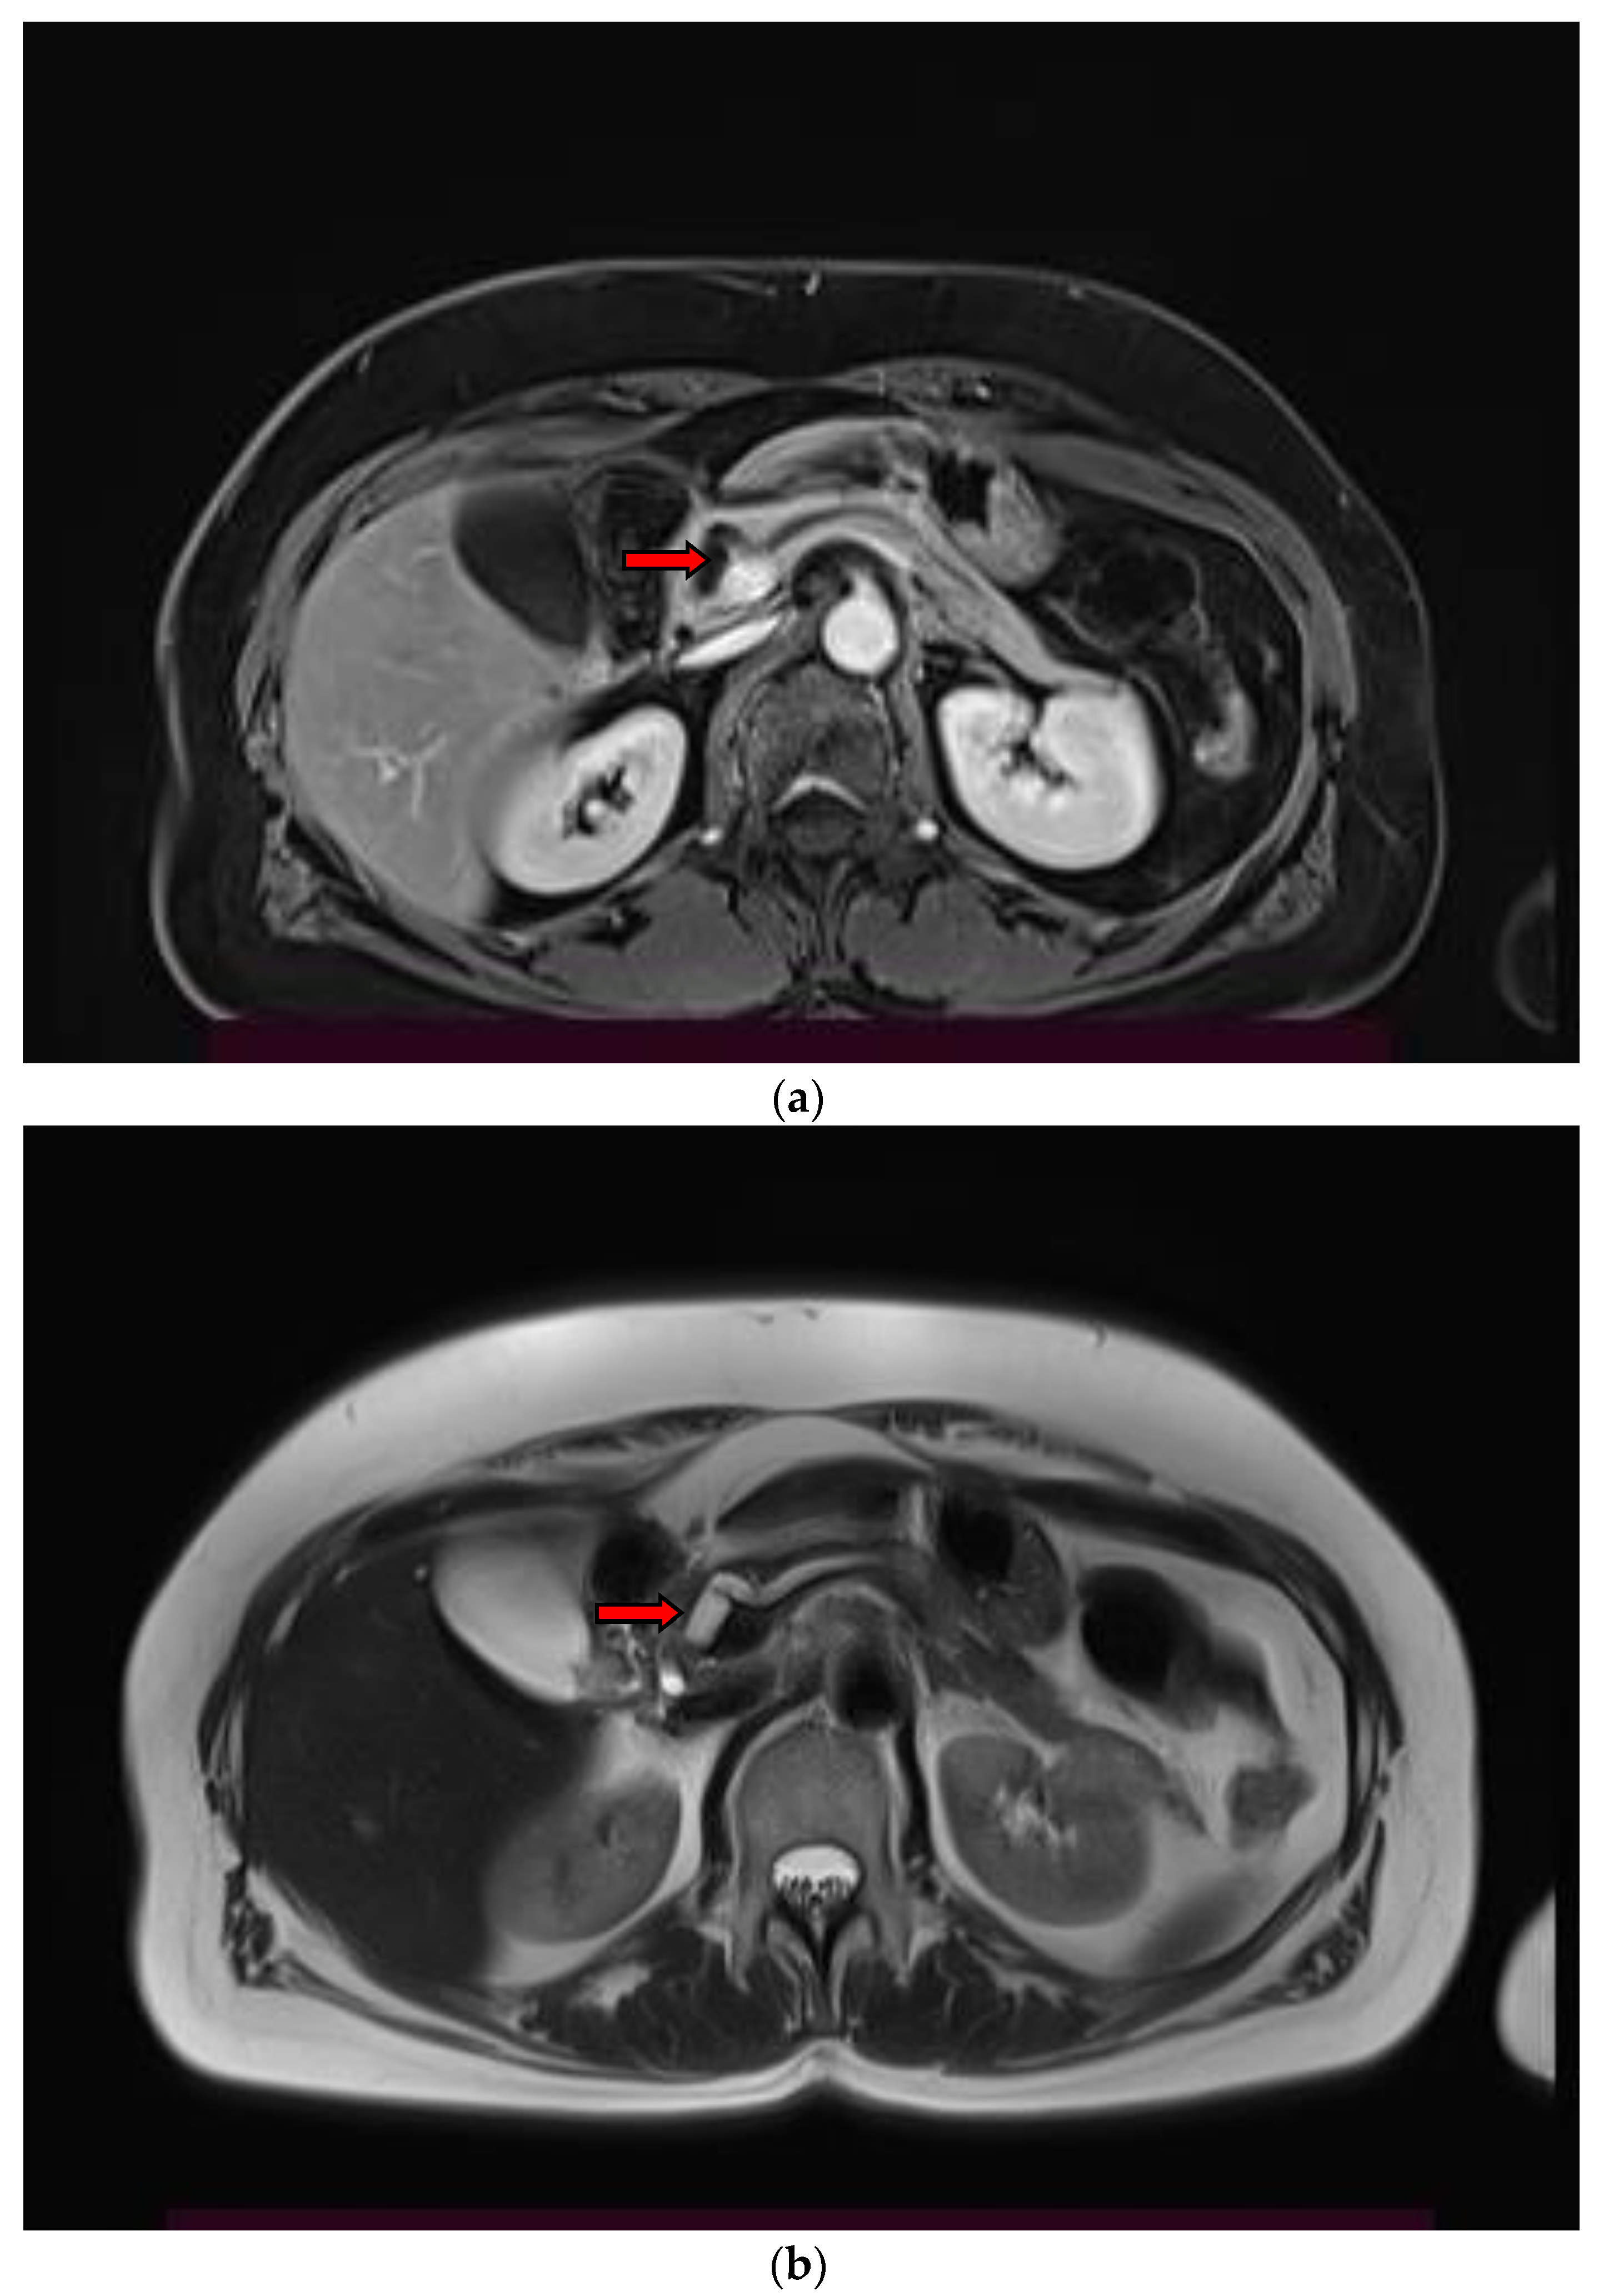

2. Imaging Findings